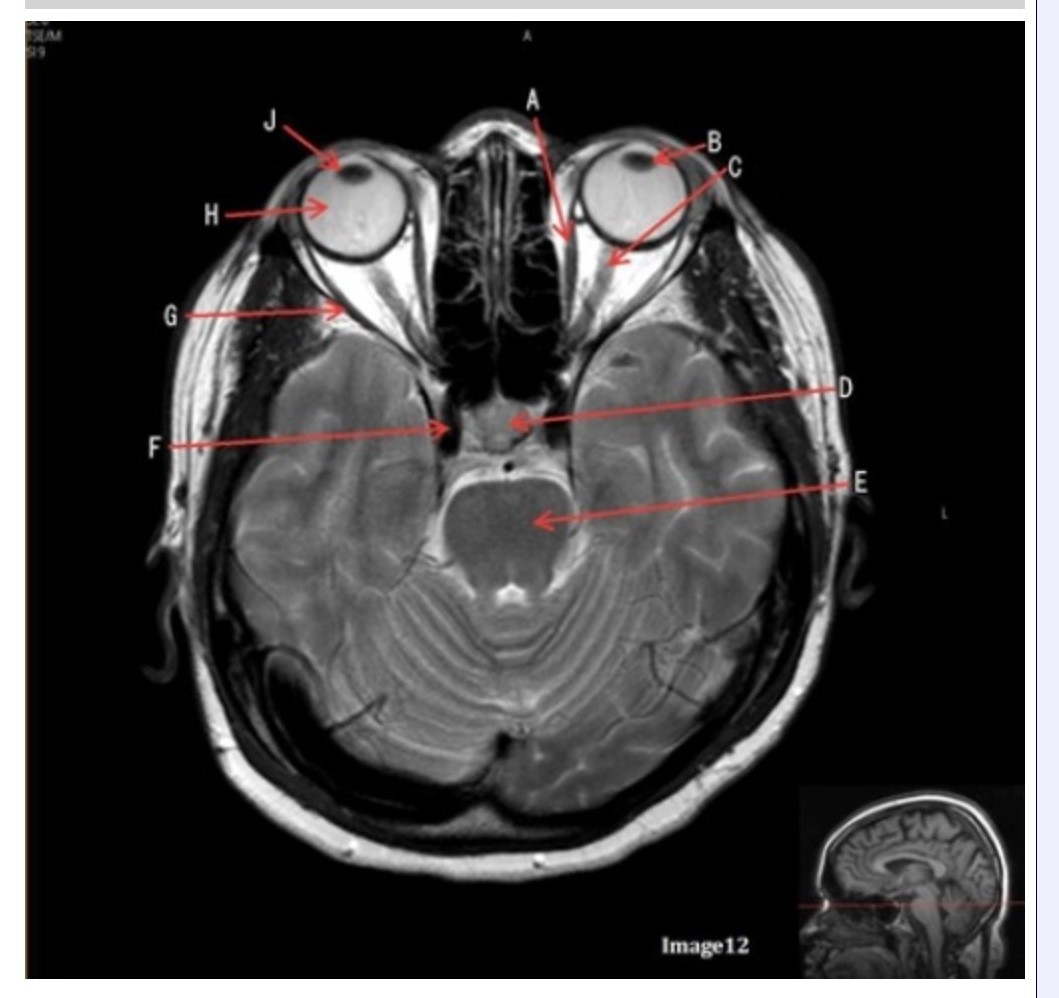

Letter H in Image 12 is pointing to:

A. Lens

B. Lateral rectus muscle

C. Medial rectus muscle

D. Internal carotid artery

E. Globe

Letter B in Image 12 is pointing to:

A. Left optic nerve

B. Lateral rectus muscle

C. Medial rectus muscle

D. Lens

E. Midbrain

Letter J in Image 12 is pointing to:

A. Globe

B. Lateral rectus muscle

C. Medial rectus muscle

D. Right lens

E. Left lens

Letter F in Image 12 is pointing to:

A. Lens

B. Lateral rectus muscle

C. Medial rectus muscle

D. Internal carotid artery

E. Globe

Letter C in Image 12 is pointing to:

A. Left optic nerve

B. Lateral rectus muscle

C. Medial rectus muscle

D. Lens

E. Midbrain

Letter D in Image 12 is pointing to:

A. Optic nerve

B. Pituitary gland

C. Globe

D. Lens

E. Midbrain

Letter G in Image 12 is pointing to:

A. Lens

B. Lateral rectus muscle

C. Medial rectus muscle

D. Internal carotid artery

E. Globe

Letter E in Image 12 is pointing to:

A. Optic nerve

B. Pituitary gland

C. Globe

D. Pons

E. Left lens